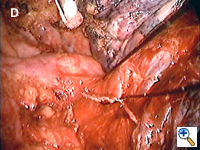

Conventional Metzenbaum scissors and DeBakey forceps are introduced through the minithoracotomy wound for sharp dissection of the hilum. The sponge holding forceps from the posterior wound is used to provide appropriate traction and to position the lobes so that the hilum can be easily accessed through the minithoracotomy. If there are adhesions of the lung to the chest wall or mediastinum, these should be taken down before starting the hilar dissection as it is essential to be able to freely move the lobes around.

If the interlobar fissure is complete or nearly complete, sharp incision of the visceral pleura and blunt dissection using a dental pledget mounted on a conventional curved clamp allow easy identification of the pulmonary artery. If the fissure is not complete, we find a monopolar diathermy forceps (Olsen Electrosurgical, Inc., Concord, CA) at a low setting to be useful for hemostasis when a layer of lung parenchyma has to be divided to access the interlobar vessels.